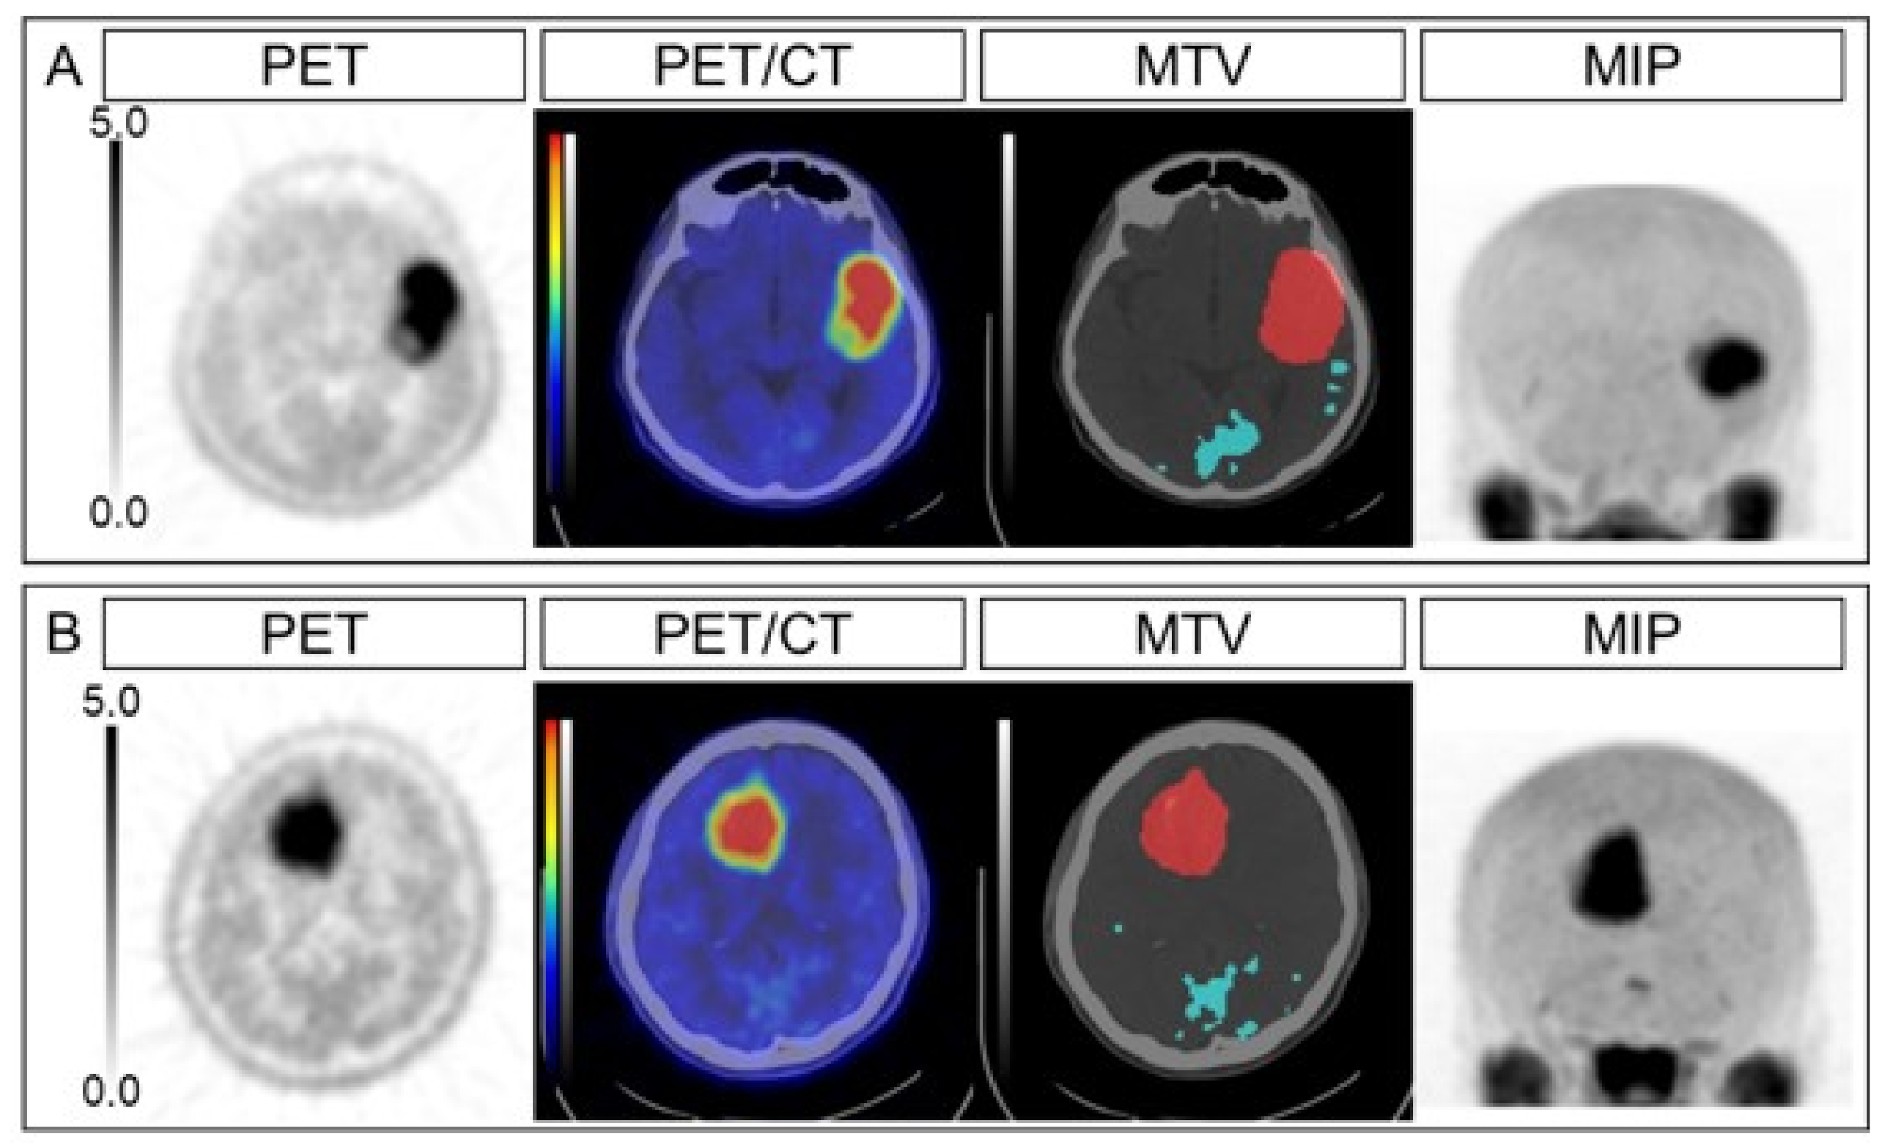

The univariate analyses revealed that OS was associated with age, tumor grade, genetic status, LGRE, and correlation, while OS was not significantly associated with sex, TNR, MTV, and TLMU (Table 3). The multivariable Cox proportional hazards models revealed that OS was independently associated with LGRE and correlation after adjusting for age (model 1), tumor grade (model 2), or genetic status (model 3) (all p < 0.05) (Table 4; Table 5). Representative cases are shown in Figure 1. The Kaplan–Meier curves revealed significantly better OS among patients with lower LGRE values (LGRE of <0.088; n = 33, p = 0.022) and lower correlation values (correlation of <1.074; n = 32, p = 0.03) (Figure 2).

Figure 1.

Representative cases. The PET, PET/CT, MTV, and MIP images are shown for an anaplastic astrocytoma case (A) and an anaplastic oligodendroglioma case (B). The SUVmax values were 7.34 and 6.87, the TNRs were 4.89 and 4.79, the MTVs were 52.7 mL and 56.3 mL, the TLMUs were 170.1 and 229.8, the LGREs were 0.118 and 0.054, and the correlations were 1.27 and 0.89, respectively, for cases (A) and (B). The overall survival intervals were 4.5 months (dead) and 31.6 months (surviving). PET, positron emission tomography; MTV, metabolic tumor volume; MIP, maximum intensity projection; SUVmax, maximum standardized uptake value; TNR, tumor-to-normal ratio; TLMU, total legion methionine uptake; LGRE, low gray-level run emphasis.